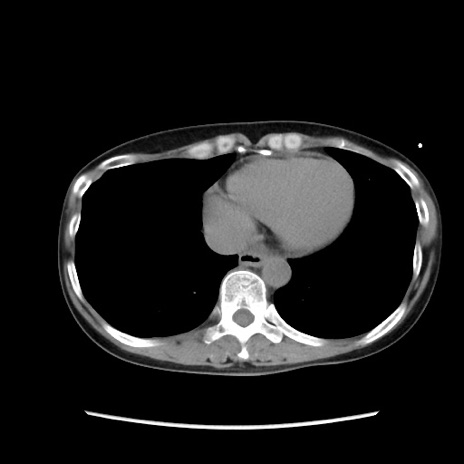

症例32(横断像)

【症例】40歳代 女性

【主訴】上腹部痛、嘔気・嘔吐

【現病歴】約9時間前頃から急に上腹部痛、嘔気、嘔吐が出現。改善しないため救急要請。

【既往歴】子宮頚癌(広汎子宮全摘術、放射線療法)、腸閉塞

【身体所見】腹部:平坦、軟、腸雑音亢進、上腹部を中心に腹部全体に圧痛あり。

【データ】WBC 8400、CRP 0.03